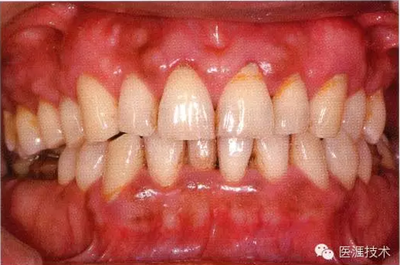

56歲牙周炎男性的臨床照片

正在服用高血壓藥中的56歲男性。菌斑控制得不好。通過牙周探診,全頜有4~6mm的牙周袋,在X光片中可以看到全頜中度牙槽骨吸收,磨牙處一個地方是重度牙槽骨吸收。通過比較牙周病進展狀態(tài),邊緣部有大范圍浮腫(發(fā)紅、腫脹),和纖維性肥厚。這也可能是服用中的降壓藥的副作用導致的。因為牙齦、牙槽骨比較厚,牙齦呈架子狀。